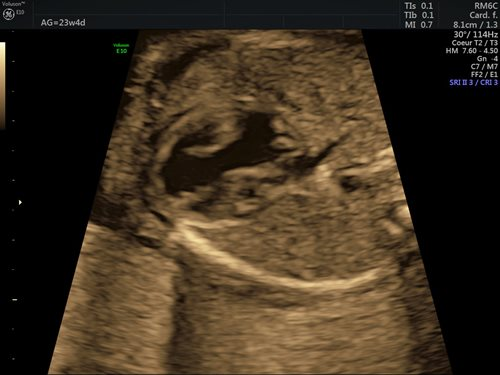

Dans la grande majorité des cas (90 %), l’étiologie des cardiopathies congénitales est multifactorielle, un facteur de risque classique comme des antécédents familiaux au 1er et 2e degré, la présence d’une anomalie chromosomique, d’un diabète maternel de type 1, d’une phénylcétonurie, la prise de certains médicaments ou une infection n’étant pas retrouvé. Pour cette raison, un dépistage systématique par échocardiographie foetale reste indispensable, idéalement entre 18 et 22 semaines de gestation. Le dépistage recommandé consiste en l’obtention d’une vue des 4 cavités cardiaques (fig. 1) et d’une vue des voies d’éjection (fig. 2). (2)

Figures 1